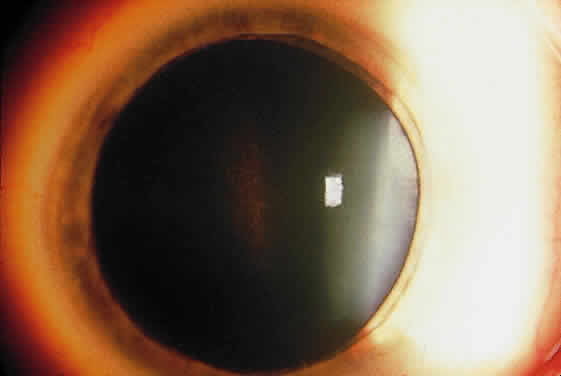

Deposition of exfoliative material on the anterior lens surface is the most commonly recognized feature of XFS and usually is best appreciated after pupillary dilation.43 A bull's-eye pattern generally is seen in which a translucent central zone and a granular peripheral zone of deposition are separated by an intermediate clear zone (Fig. 1). The translucent central zone of exfoliative material varies in diameter and may exhibit curled edges. In approximately 20% of patients with exfoliation, the central zone may be absent.38 The intermediate clear zone presumably results from lens contact with movement of the iris. The granular peripheral zone, which may be subtle but invariably is present in XFS, generally exhibits a well-delineated inner border and often shows numerous radial striations (Fig. 2). Occasionally, a bridge of exfoliative material may cross the clear zone to join the central zone and the granular peripheral zone.38,44